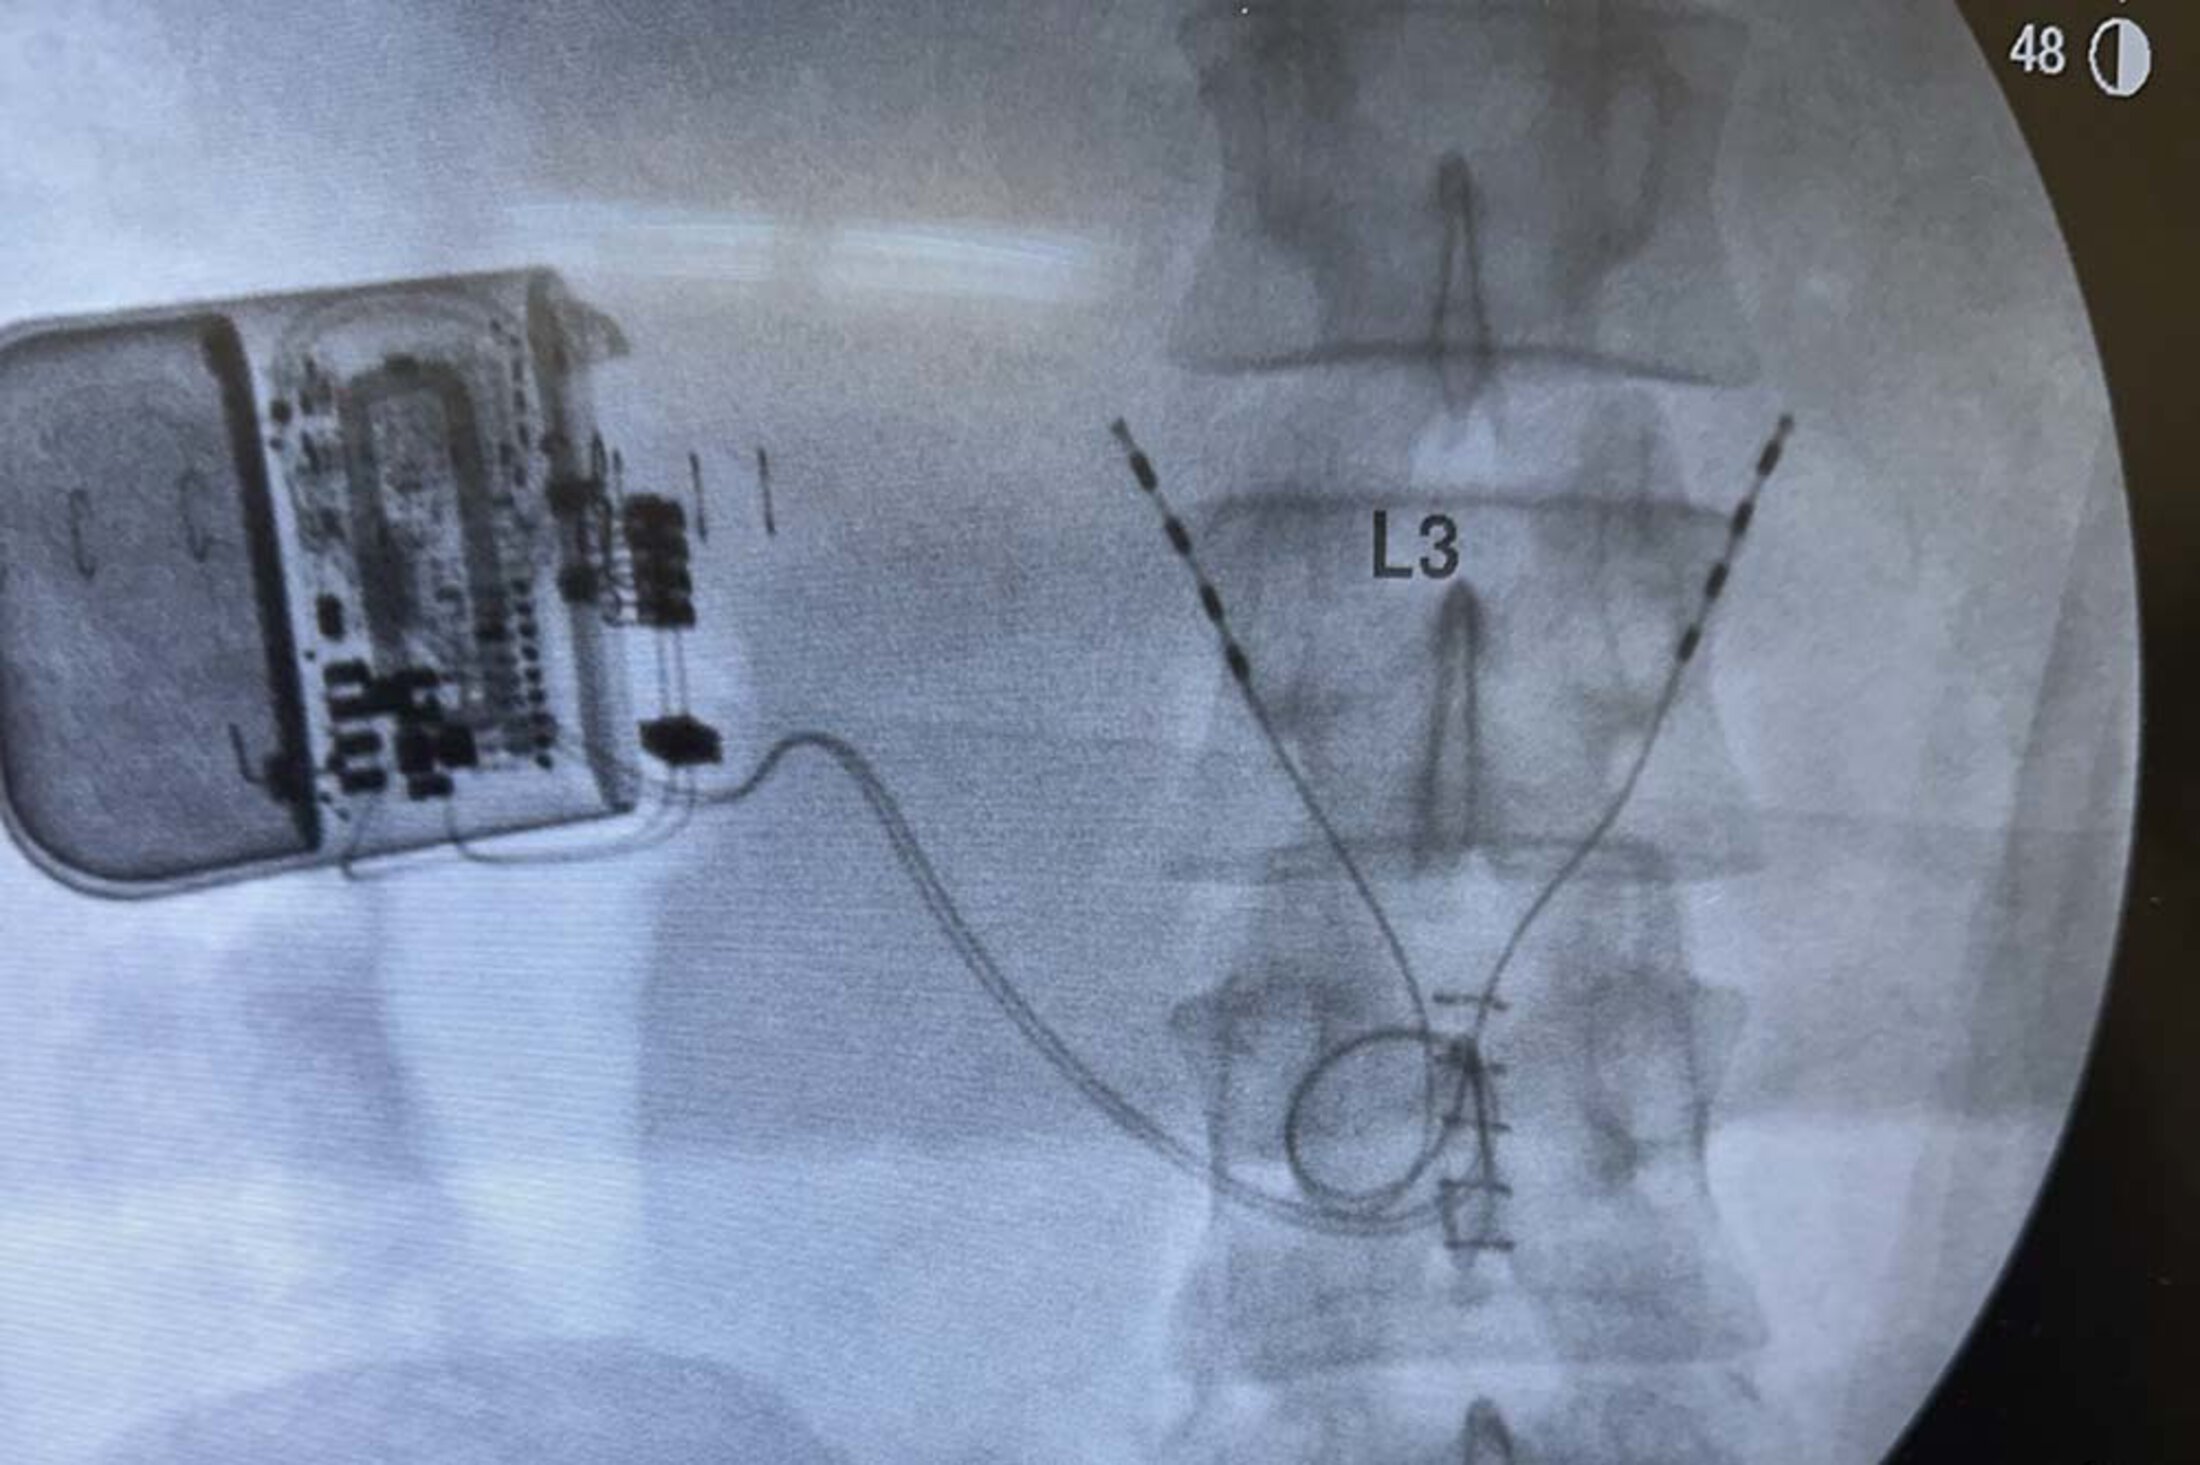

A source of relief for a different group of patients involves a device called ReActiv8. “It's basically a treatment option for folks with a specific type of low back pain that is caused by the muscles in their low back not functioning appropriately. It’s for people when conservative care, physical therapy, hasn't restored that function,” Burke said.

ReActiv8 is a neurostimulator that not only relieves pain but also restores muscle function and improves physical function. Photo provided

“It's similar to a spinal cord stimulator. It works very differently, but it's similar in that it's a battery and two wires that are implanted. And it causes the muscles to stimulate and contract, which regains their function over time. There's no other treatment in our field that is similar to it. I'm passionate about that one because it works so well.”p>